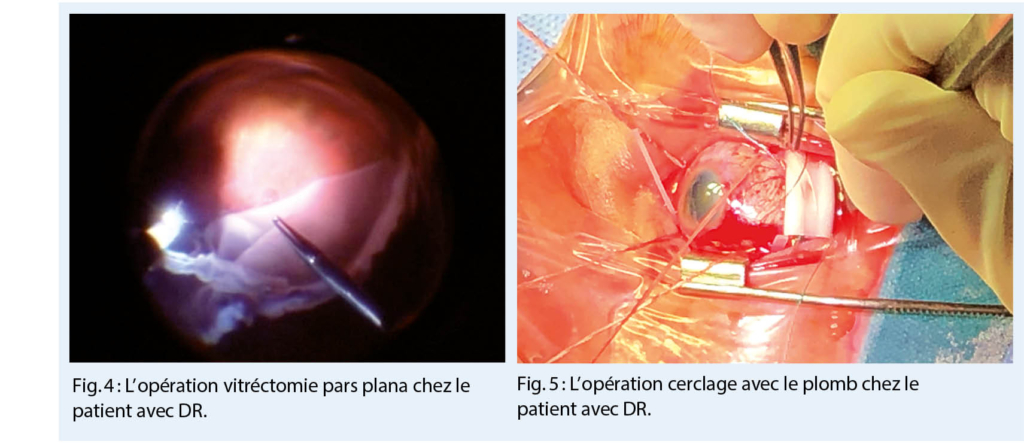

Il existe deux types de chirurgie pour le DR (9) :

- la vitréctomie pars plana (PPV)

- le cerclage

La base des deux méthodes chirurgicales est la fermeture de toutes les déchirures rétiniennes (par kryopexie, ou par laser-photocoagulation), le drainage du liquide sous-rétinien et la tamponnade postopératoire, qui est principalement utilisée dans le PPV (9, 10).

La technique le plus souvent utilisée est la PPV (fig. 4). Elle implique une approche intraoculaire. Avec le développement des instruments ces dernières vingt années, le taux de réussite des opérations a augmenté de façon significative (10). Aujourd’ hui, la PPV est réalisée en plaçant des trocarts (trois ou éventuellement quatre petits tunnels de 23G, 25G ou 27G) à travers la sclère, au niveau pars plana. Les trocarts servent à réaliser la partie principale de l’ opération, c’ est-à-dire, pour entrer dans l’ œil avec des instruments afin d’ enlever le vitré, aspirer le liquide sous-rétinien, fermer les déchirures et ajouter des agents pour tamponner la rétine (gaz ou l’ huile de silicone). Certains agents de tamponnade restent dans l’ œil jusqu’à ce qu’ ils soient résorbés (air ou différents gaz, qui sont expansibles) ou jusqu’ à ce qu’ils soient éliminés par une nouvelle intervention chirurgicale (l’ huile de silicone) (9, 10). Après l’ opération, durant la première semaine, le positionnement du patient est très important, afin de bien « repasser la rétine » et éliminer le liquide sous-rétinien (9).

Le cerclage est une méthode plus ancienne toujours utilisée dans certaines indications (fig. 5) (10). Il s’ agit d’ une approche externe, sans entrer dans l’ œil. Cette technique est préférable chez les jeunes patients. Une fois que la projection sclérale de la déchirure rétinienne est localisée par ophtalmoscopie indirecte, la kryopexie est réalisée au même endroit afin de créer une cicatrice. Au même endroit, un plomb est placé, suturé à la sclère. Le plomb va fermer la déchirure par l’ extérieur. Aussi, chez certains patients, le cerclage (comme une ceinture) est placé sous les muscles extra-oculaires droits, pour diminuer la traction circulaire entre le vitré et la rétine (10).